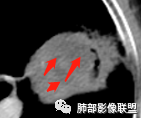

空洞内侧软组织肿块,比较支持恶性吧

这个空洞的性质很重要,对最后诊断结果影响大,如果中间没有曲菌球,那就是偏心空洞,指向恶性,如果是曲菌球引起的新月形改变,那就不一定。至于到底是曲菌球还是偏心空洞,需要仔细看看强化情况。

2、偏心空腔病灶,气腔略呈新月形,壁不规则,腔内结节相对密实,明显强化且不均,支持新生物而非曲菌球等。炎性空洞多有强化环。